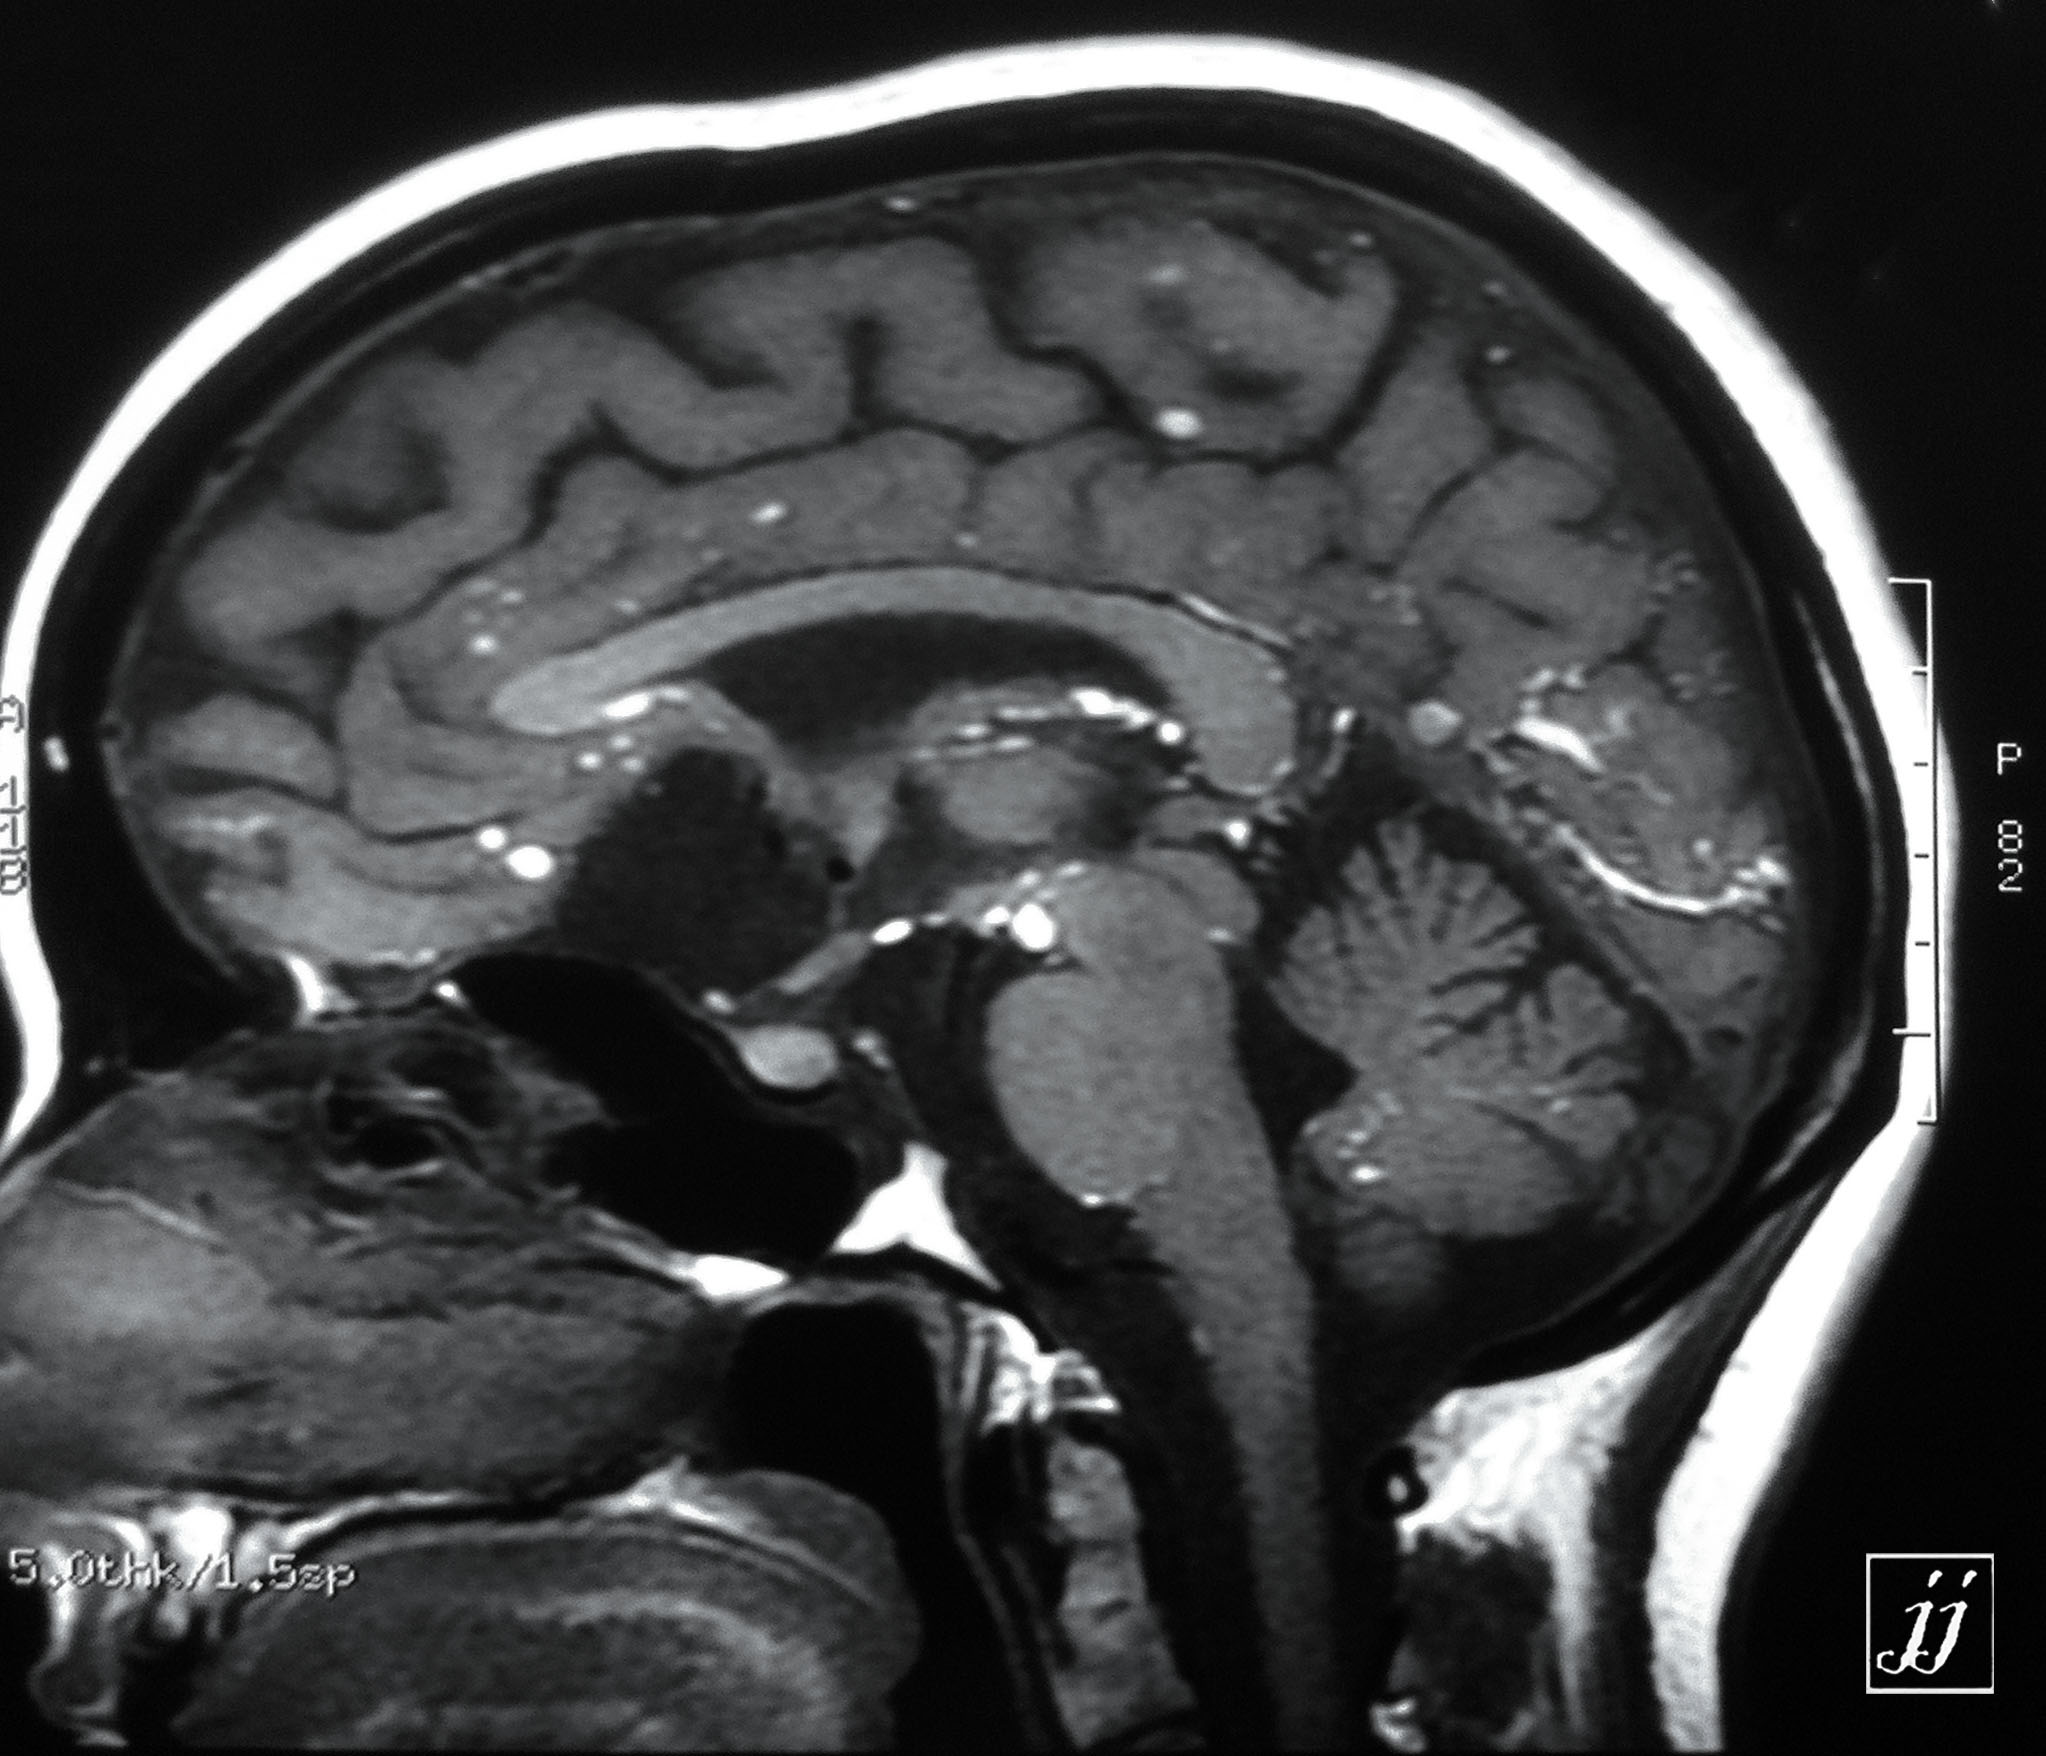

Brain- opac material in cisterns (9)